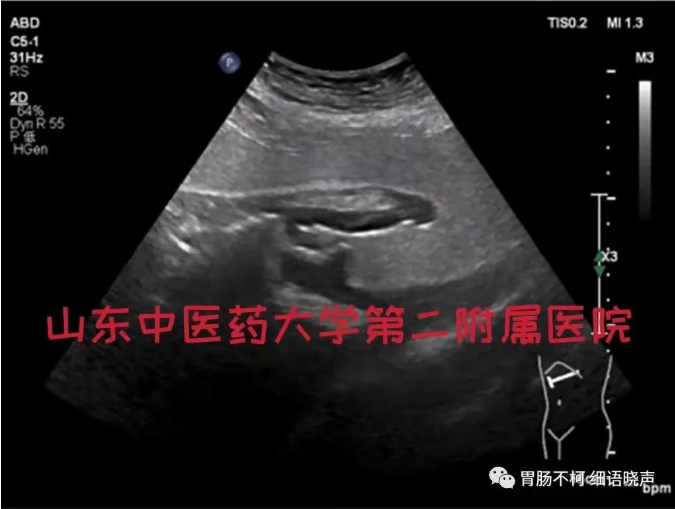

病例一,胃体前壁胃壁增厚性病变: